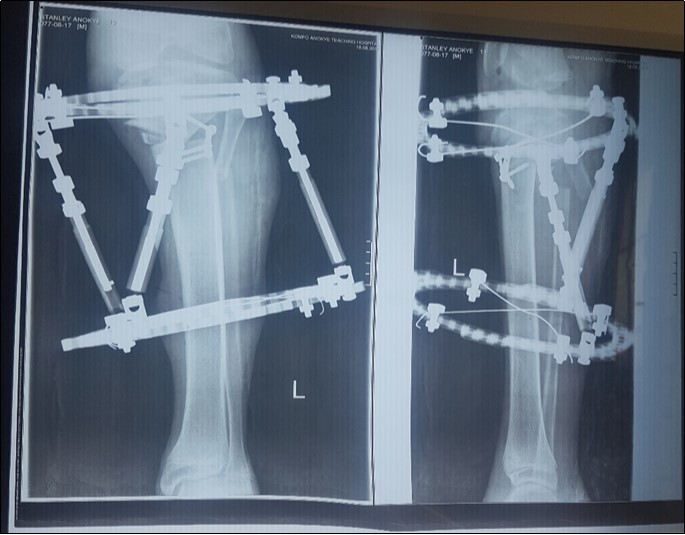

In this report we present our correction procedure for Langenskiold Type VI with a single-stage double tibial osteotomy and maintenance of correction of deformity with a Taylor Spatial Frame. Figure 5, Figure 6.

Figure 5.Immediate post-operative picture of the patient lying on the operating table.

Figure 6.Post-operative x-ray showing the proximal tibia and the fibula osteotomy as well as the Taylor Spatial Frame.